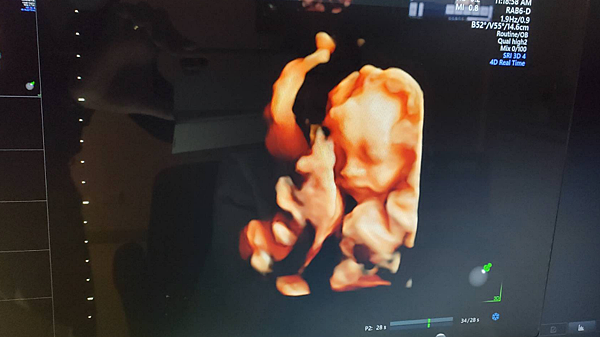

文章最後加碼彩蛋~~妹妹的超音波照現身啦

比起哥哥的超音波 她真的有夠難照的

常常都躲起來不給我們看臉 難得才現身一下 哈哈

目前只看得出來肉呼呼的臉頰還有翹嘟嘟的嘴唇

感覺跟哥哥有夠像(爸爸媽媽已經昏倒 妹妹可以長得女生氣一點嗎哈哈)~